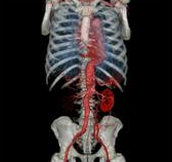

Body angiography with automatic table removal ? colored volume rendering reconstruction. Case: Aortic dissection. Left common iliac artery occlusion. Scanning: P0.83, 0.5s, 360mA, 100kV, weight 80kg, contrast 80cc